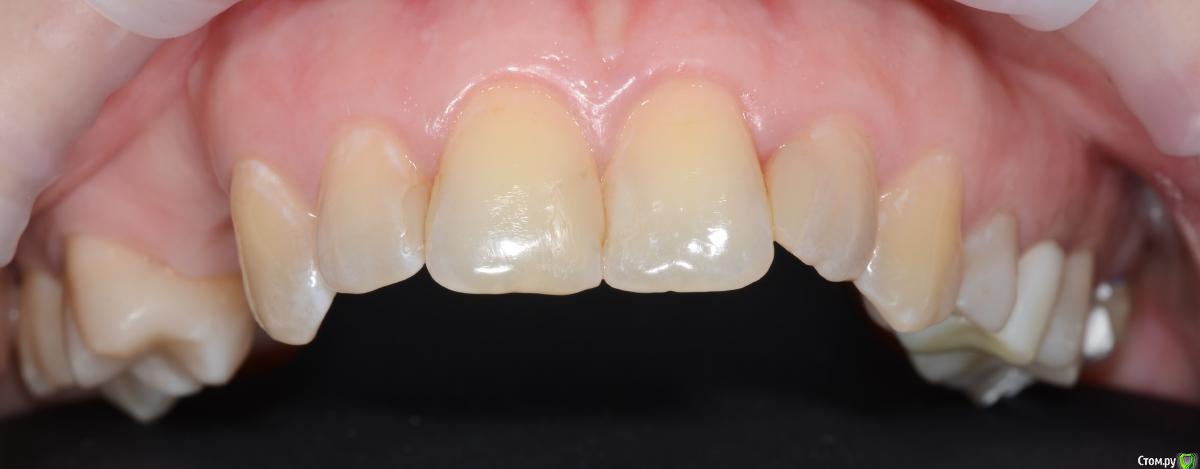

Foxtrot Опубликовано 29 августа, 2018 Поделиться Опубликовано 29 августа, 2018 Доброго времени суток! Как думаете стоит ли устанавливать 2 импланта, удастся ли добиться эстетики мягких тканей? Как бы вы поступили в данной ситуации? У меня пока 3 варианта:1) нкр + импланты - первым этапом, десна - вторым.2) нкр + сст - первым, времянки и еще десна (по ситуации) - вторым.3) 1 имплант, сст, времянка с консолью.Все в один этап как-то страшновато. Ссылка на комментарий

Podarev Опубликовано 29 августа, 2018 Поделиться Опубликовано 29 августа, 2018 Судя по фото пациент девушка. Какие эстетические требования предъявляет? Менее рисково по третьему плану пойти, но готовиться к высокой коронке на 14. В случае широкой улыбки могут возникать вопросы. Теоретически два по 3.0 проходят, но тогда все четко ставить надо Ссылка на комментарий

Foxtrot Опубликовано 29 августа, 2018 Автор Поделиться Опубликовано 29 августа, 2018 Судя по фото пациент девушка. Какие эстетические требования предъявляет? Менее рисково по третьему плану пойти, но готовиться к высокой коронке на 14. В случае широкой улыбки могут возникать вопросы. Теоретически два по 3.0 проходят, но тогда все четко ставить надоДа, вы правы, пациент девушка 30 лет. Эстетические требования - умеренно высокие. По поводу третьего варианта, интересует долговечность конструкции, где-то читал что имеют место быть раскручивания и переломы. Ссылка на комментарий